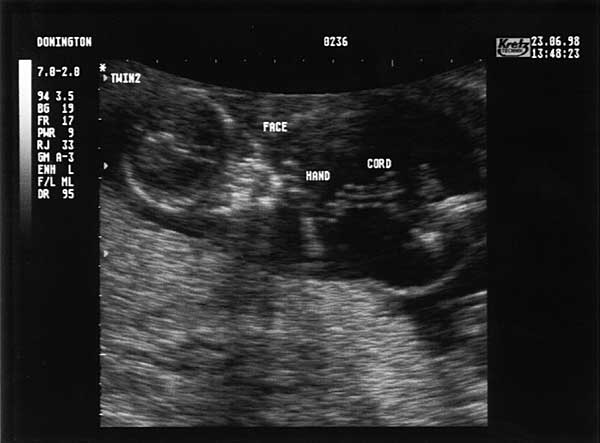

13 Weeks - Tuesday 23rd June 1998 (approx 75mm)

Thirteen Week Scan 1

Looking down along length of Twin 2's (Lucy's) body. Top of head and face at top left, right arm and hand near chin. Umbilical cord and leg to the right.